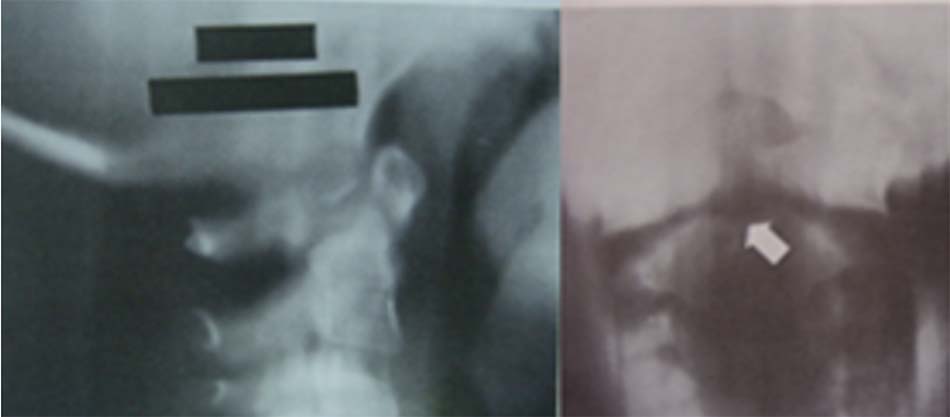

- Không có mỏm nha: là dị tật mỏm nha không phát triển, trên Xquang thường quy không có mỏm nha.

Hình 1.35. Hình ảnh Xquang không có mỏm nha. - Thiểu sản mỏm nha: mỏm nha phát triển bán phần, có hình dạng khác nhau có thể là 1 mẩu ngắn hoặc có thể có kích thước gần như bình thường.

Hình 1.36. Thiểu sản mỏm nha trên Xquang - Khớp giả mỏm nha: Mỏm nha được chia làm 2 đoạn, trong đó có một đoạn tách rời.

Hình 1.37. Mất vững C1-C2, khớp giả mỏm nha trên Xquang thường quy